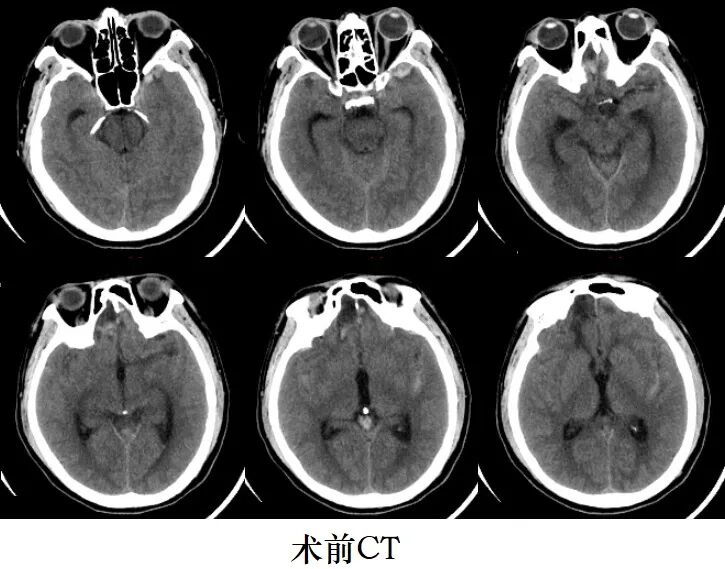

近日,家住阜宁的邵先生因突发头疼伴神志不清入住盐城市第一人民医院北院区神经外科,经神经外科博士、副主任医师孟成杰结合患者病史、内分泌检查、CT及DSA等检查,诊断为患者存在双侧后交通动脉及左侧大脑中动脉多发动脉瘤,且左侧后交通动脉瘤破裂出血。

颅内动脉瘤,是大脑内部动脉血管异常膨出后形成的动脉瘤,就像是血管上长了一颗葡萄,里面充盈着血液,一旦破裂,危及性命,因此被称为颅内的“不定时炸弹”,首次破裂死亡率极高,并且随时可再发破裂出血导致患者死亡,即使通过及时抢救,往往会遗留严重后遗症。 患者脑多发动脉瘤中有大脑中动脉瘤,而大脑中动脉瘤治疗首选手术夹闭,同时患有双侧脑多发动脉瘤十分罕见,传统会选择介入栓塞或分次双侧开颅手术,这不仅增加患者经济负担,还增加患者的手术创伤,且传统翼点入路开颅手术创伤大,并发症多,恢复慢。情况危急,邵先生随时可能因动脉瘤再发破裂导致出血死亡。盐城市一院神经外科孟成杰专家团队针对邵先生的病情,立即与患者家属充分沟通后,决定使用眶上外侧入路微创手术治疗邵先生的双侧多发动脉瘤,争取一次微创显微手术解决患者双侧多发病灶,防止动脉瘤再发破裂,挽救患者生命。 经过充分的术前准备,在麻醉科手术团队的紧密配合下,为了尽可能减少手术对邵先生的创伤,孟成杰采用左侧眶上外侧入路,保护好颞肌及面神经分支等,术中充分分离外侧裂,暴露好左侧大脑中动脉瘤后予以顺利夹闭,然后抬起额叶从第二间隙夹闭左侧后交通破裂动脉瘤,最后在视交叉前间隙夹闭对侧后交通动脉瘤,手术全程历时约3.5小时。术后第二天患者神志恢复清醒且无任何后遗症,术后复查CTA提示双侧后交通动脉及左侧大脑中动脉多发动脉瘤夹闭完全,目前,患者痊愈出院。 孟成杰专家团队使用眶上外侧入路开颅手术相比传统翼点入路开颅手术创伤明显减小,骨窗仅5厘米左右,而传统翼点入路骨窗要12~15厘米左右,同时该团队一次微创手术解决患者双侧脑多发动脉瘤达到国内先进水平。盐城市一院神经外科率先在盐城地区开展眶上外侧入路手术技术,到目前为止,孟成杰专家团队已应用该技术成功手术治疗数十例颅内复杂动脉瘤及颅内肿瘤患者,并获得盐城市医学新技术引进一等奖。该技术具有创伤小、恢复快、并发症少等优点,通过该微创手术治疗从源头上解决颅内病变,让患者尽早恢复正常工作生活。